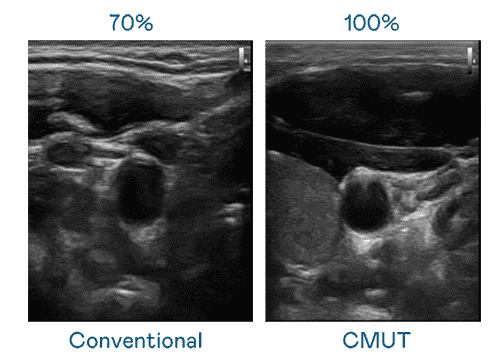

CMUT 技术是一种用电容式微机电元件来产生超音波讯号的技术。。与传统 PZT 压电式技术相比,,,CMUT 频宽增加 30%,,更宽频的超音波讯号让影像解析度大幅提升,,,是实现高影像品质医疗超音波扫描、、促进精准医疗发展的关键技术。。。

超音波影像的解析度高低,,,首先取决于探头能发出的讯号频宽。。。。森林舞会 CMUT 可提供高清晰的超音波讯号,,,提供高频宽、、、、高灵敏度、、影像纹理细节更高的超音波影像,,,,协助医护人员缩短影像判读时间及利用精准的医疗影像进行诊断。。。。